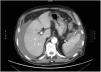

A 77-year-old man had a history of GOLD III chronic obstructive pulmonary disease, lung adenocarcinoma with no current evidence of recurrence, atrial flutter (anticoagulation with edoxaban), prostatectomy due to adenocarcinoma, cholecystectomy, and right inguinal hernioplasty. He sought medical attention for diarrhea, asthenia, and weight loss of several months of progression. Upon admission, oral anticoagulation was suspended and substituted with enoxaparin (60 mg/12 h). Diagnostic colonoscopy was performed, with the patient under deep sedation with propofol. There was no technical difficulty or immediate complications, and the only finding was diverticulosis. No pressure was applied on the left upper quadrant of the abdomen. Twelve hours after the procedure, the patient presented with low blood pressure, tachycardia, and generalized abdominal pain that was poorly controlled with opioids. The pain was described as progressively worsening over several hours. Emergency laboratory tests showed anemia of 8.4 g/dl (previously 12.9 g/dl) and an abdominal x-ray ruled out perforation. Emergency abdominal CT scan was carried out (Fig. 1) that identified splenic rupture with extravasation of the active contrast medium, a large peri-splenic hematoma, and moderate hemoperitoneum, corresponding to a grade V splenic injury, according to the American Association for the Surgery of Trauma (AAST). Despite intensive fluid therapy, the hemodynamic instability persisted, and so emergency splenectomy was performed.

Splenic rupture following colonoscopy is a rare, but potentially serious, complication, with 100 cases described and an estimated incidence of 1 out of every 100,000 procedures.1 Among the apparently associated risk factors are female sex, advanced age, a history of abdominal/pelvic surgery, and anticoagulant/antiplatelet treatment.2 Its etiology is not fully understood, but 3 possible mechanisms have been postulated: direct trauma to the spleen; traction on the splenocolic ligament; or traction on splenocolic adhesions secondary to inflammation or previous surgery.3,4 It usually manifests as abdominal pain in the left hypochondrium, with or without Kehr’s sign (pain radiating to the left shoulder), anemia, and hemodynamic instability.5 The role of deep sedation, which is increasingly used and could mask or delay the appearance of pain, is not clear. When splenic rupture is suspected, the study of choice is contrast-enhanced abdominal CT, albeit abdominal ultrasound can also be useful.